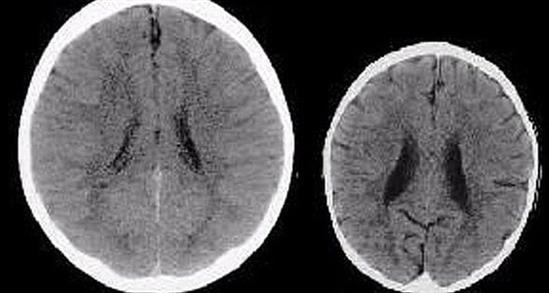

Cụ thể hơn, dưới đây là não của 2 đứa trẻ 3 tuổi. Chỉ cần thoáng quan sát, ai cũng nhận ra bộ não bên trái lớn hơn rất nhiều, đúng không?

Tấm phim chụp này đã được nhiều nhà thần kinh học sử dụng để nghiên cứu. Theo đó, bộ não bên phải thiếu đi rất nhiều khu vực cơ bản, và sự thiếu hụt này có thể gây ảnh hưởng nghiêm trọng đến sự phát triển của trẻ sau này.

Đứa trẻ thiếu may mắn khi trưởng thành sẽ kém thông minh hơn, khả năng đồng cảm thấp hơn, có xu hướng sử dụng chất kích thích nhiều hơn, và thiên hướng bạo lực cũng gia tăng. Bé cũng dễ trở thành đối tượng thất nghiệp, phải sống nhờ trợ cấp xã hội, đồng thời phải gánh chịu tương lai chứa nhiều bệnh tật phía trước.

Rất tiếc là không phải! Các chuyên gia cho biết, lý do làm nên sự khác biệt này đến từ các bà mẹ, mà cụ thể là cách chăm sóc của mẹ với bé. Đứa trẻ bên trái nhận được đầy đủ sự yêu thương, chăm sóc và trách nhiệm, trong khi đứa trẻ thiếu may mắn kia sống trong bạo hành và gần như bị bỏ bê hoàn toàn.